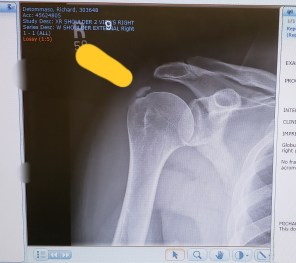

We meet with an orthopedic and he tells us that the floating calcification he sees on the x-ray may have been in his shoulder before; we have no slides to tell us when this occurred. His take is that we just need to allow the inflammation to go down and see how Rich’s shoulder feels from there. A well placed cortisone shot helps in the days to come and Rich is advised to do mild exercises as home physical therapy to avoid frozen shoulder syndrome.